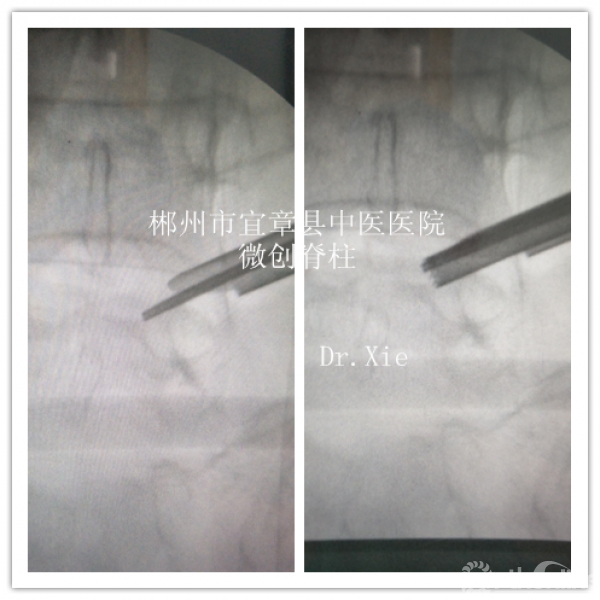

成型后置管透视情况

置管成功后,镜下结构: